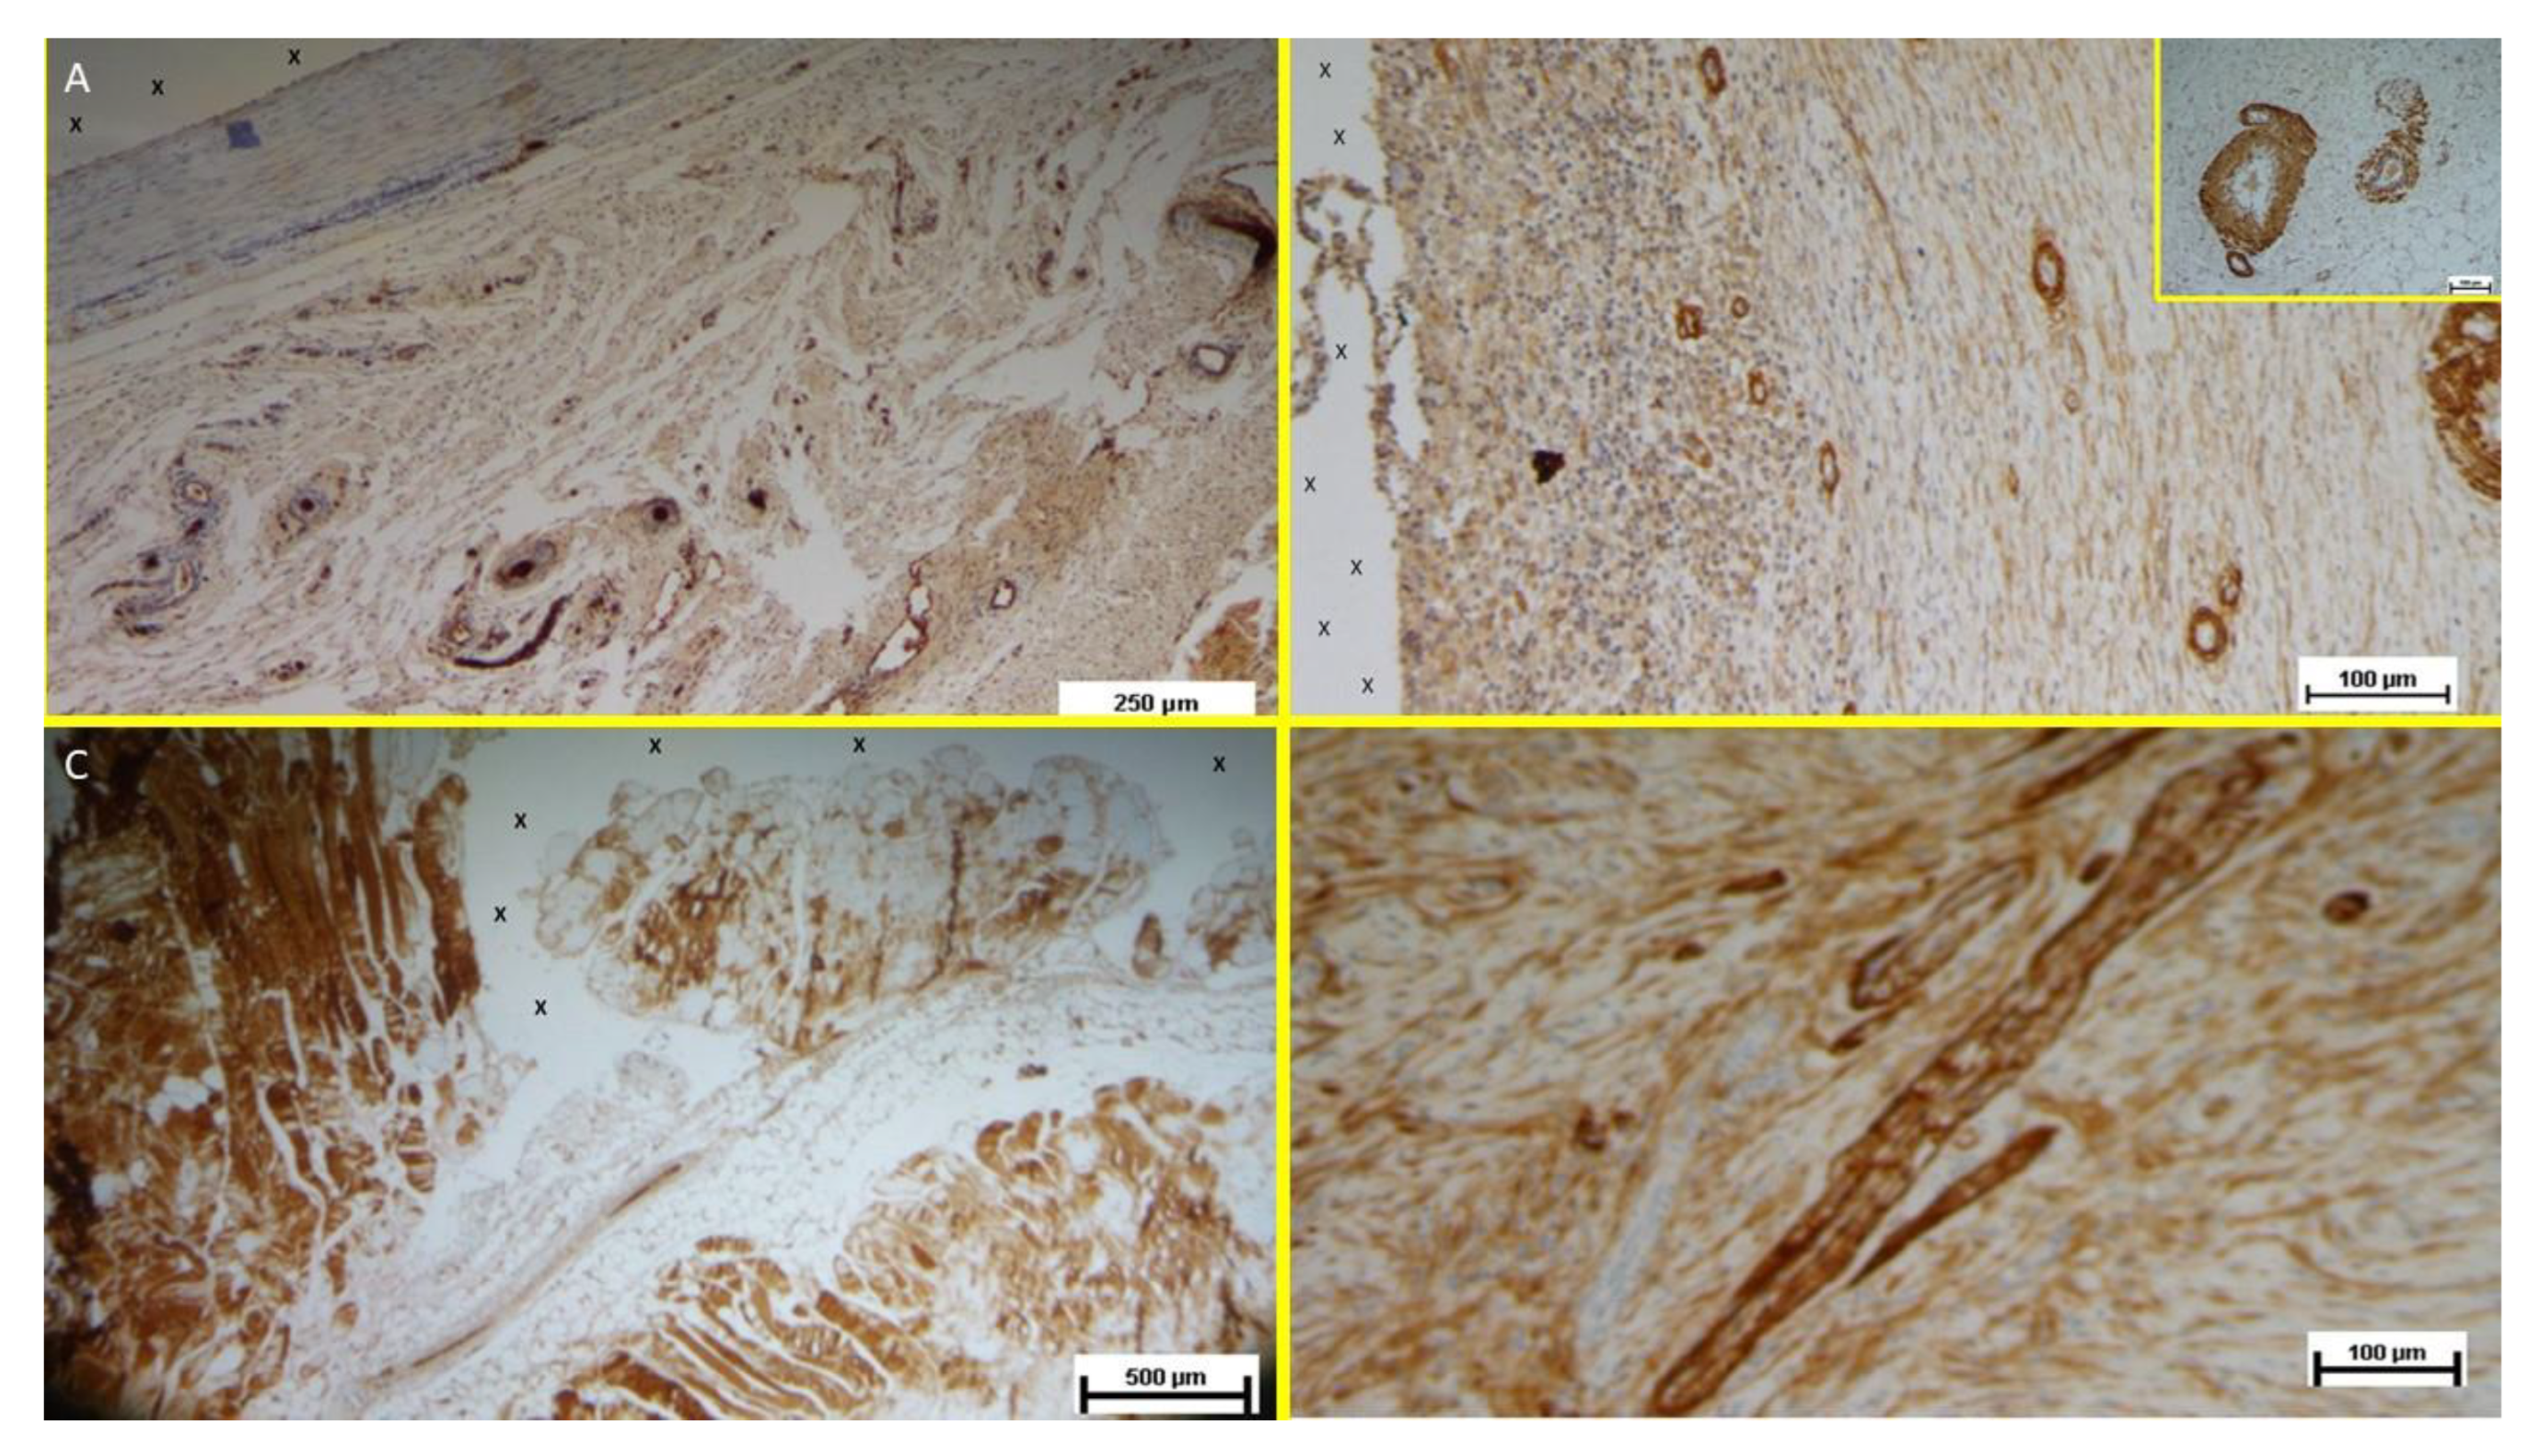

Figure 12.

A: Tissue sample removed from the 3D scaffold of the S&D device six months implantation. Numerous clusters of intense neo-angiogenesis (colored in brown) with well-developed vascular structures are clearly evident close to the device fabric (X). CD31 50X - B: Tissue sample excised from the 3D scaffold of the S&S device 8 months post-surgery. Numerous venous elements showing well-constituted muscular layer are highlighted close to the scaffold fabric (X). SMA 100X - The high magnification microphotograph in the right upper corner depicts two arterial structures with a well-represented muscular layer (colored in brown). SMA 200X - C: Biopsy sample excised from the scaffold of the S&S device 6 months post implantation. The image shows plenty of muscular elements (colored in brown) grouped in bundles close to the TPE structure of the device. NGF 25X - D: Biopsy specimen excised from the 3D scaffold of the S&S device 6 months post-implantation. The image shows a mature elongated nervous structure (colored in brown) developed within the TPE scaffold. NGFRp75 100X.

Figure 12 A). Long-term specimens exhibited further SMA-mediated structural thickening, with complete vascular development (

Figure 12 B).

Muscular Growth Factors: NGF-positive elements indicated muscular development in the early stage, increasing in quantity and organization into bundles by the mid and long term (

Figure 12 C).

Nervous Growth Factors: NGFRp75-positive neural elements were initially sparse, correlating with immature nervous clusters. By the midterm, these elements increased, showing progressive myelin sheath development. Long-term specimens revealed mature nerve structures resembling human nerves (

Figure 12 D).